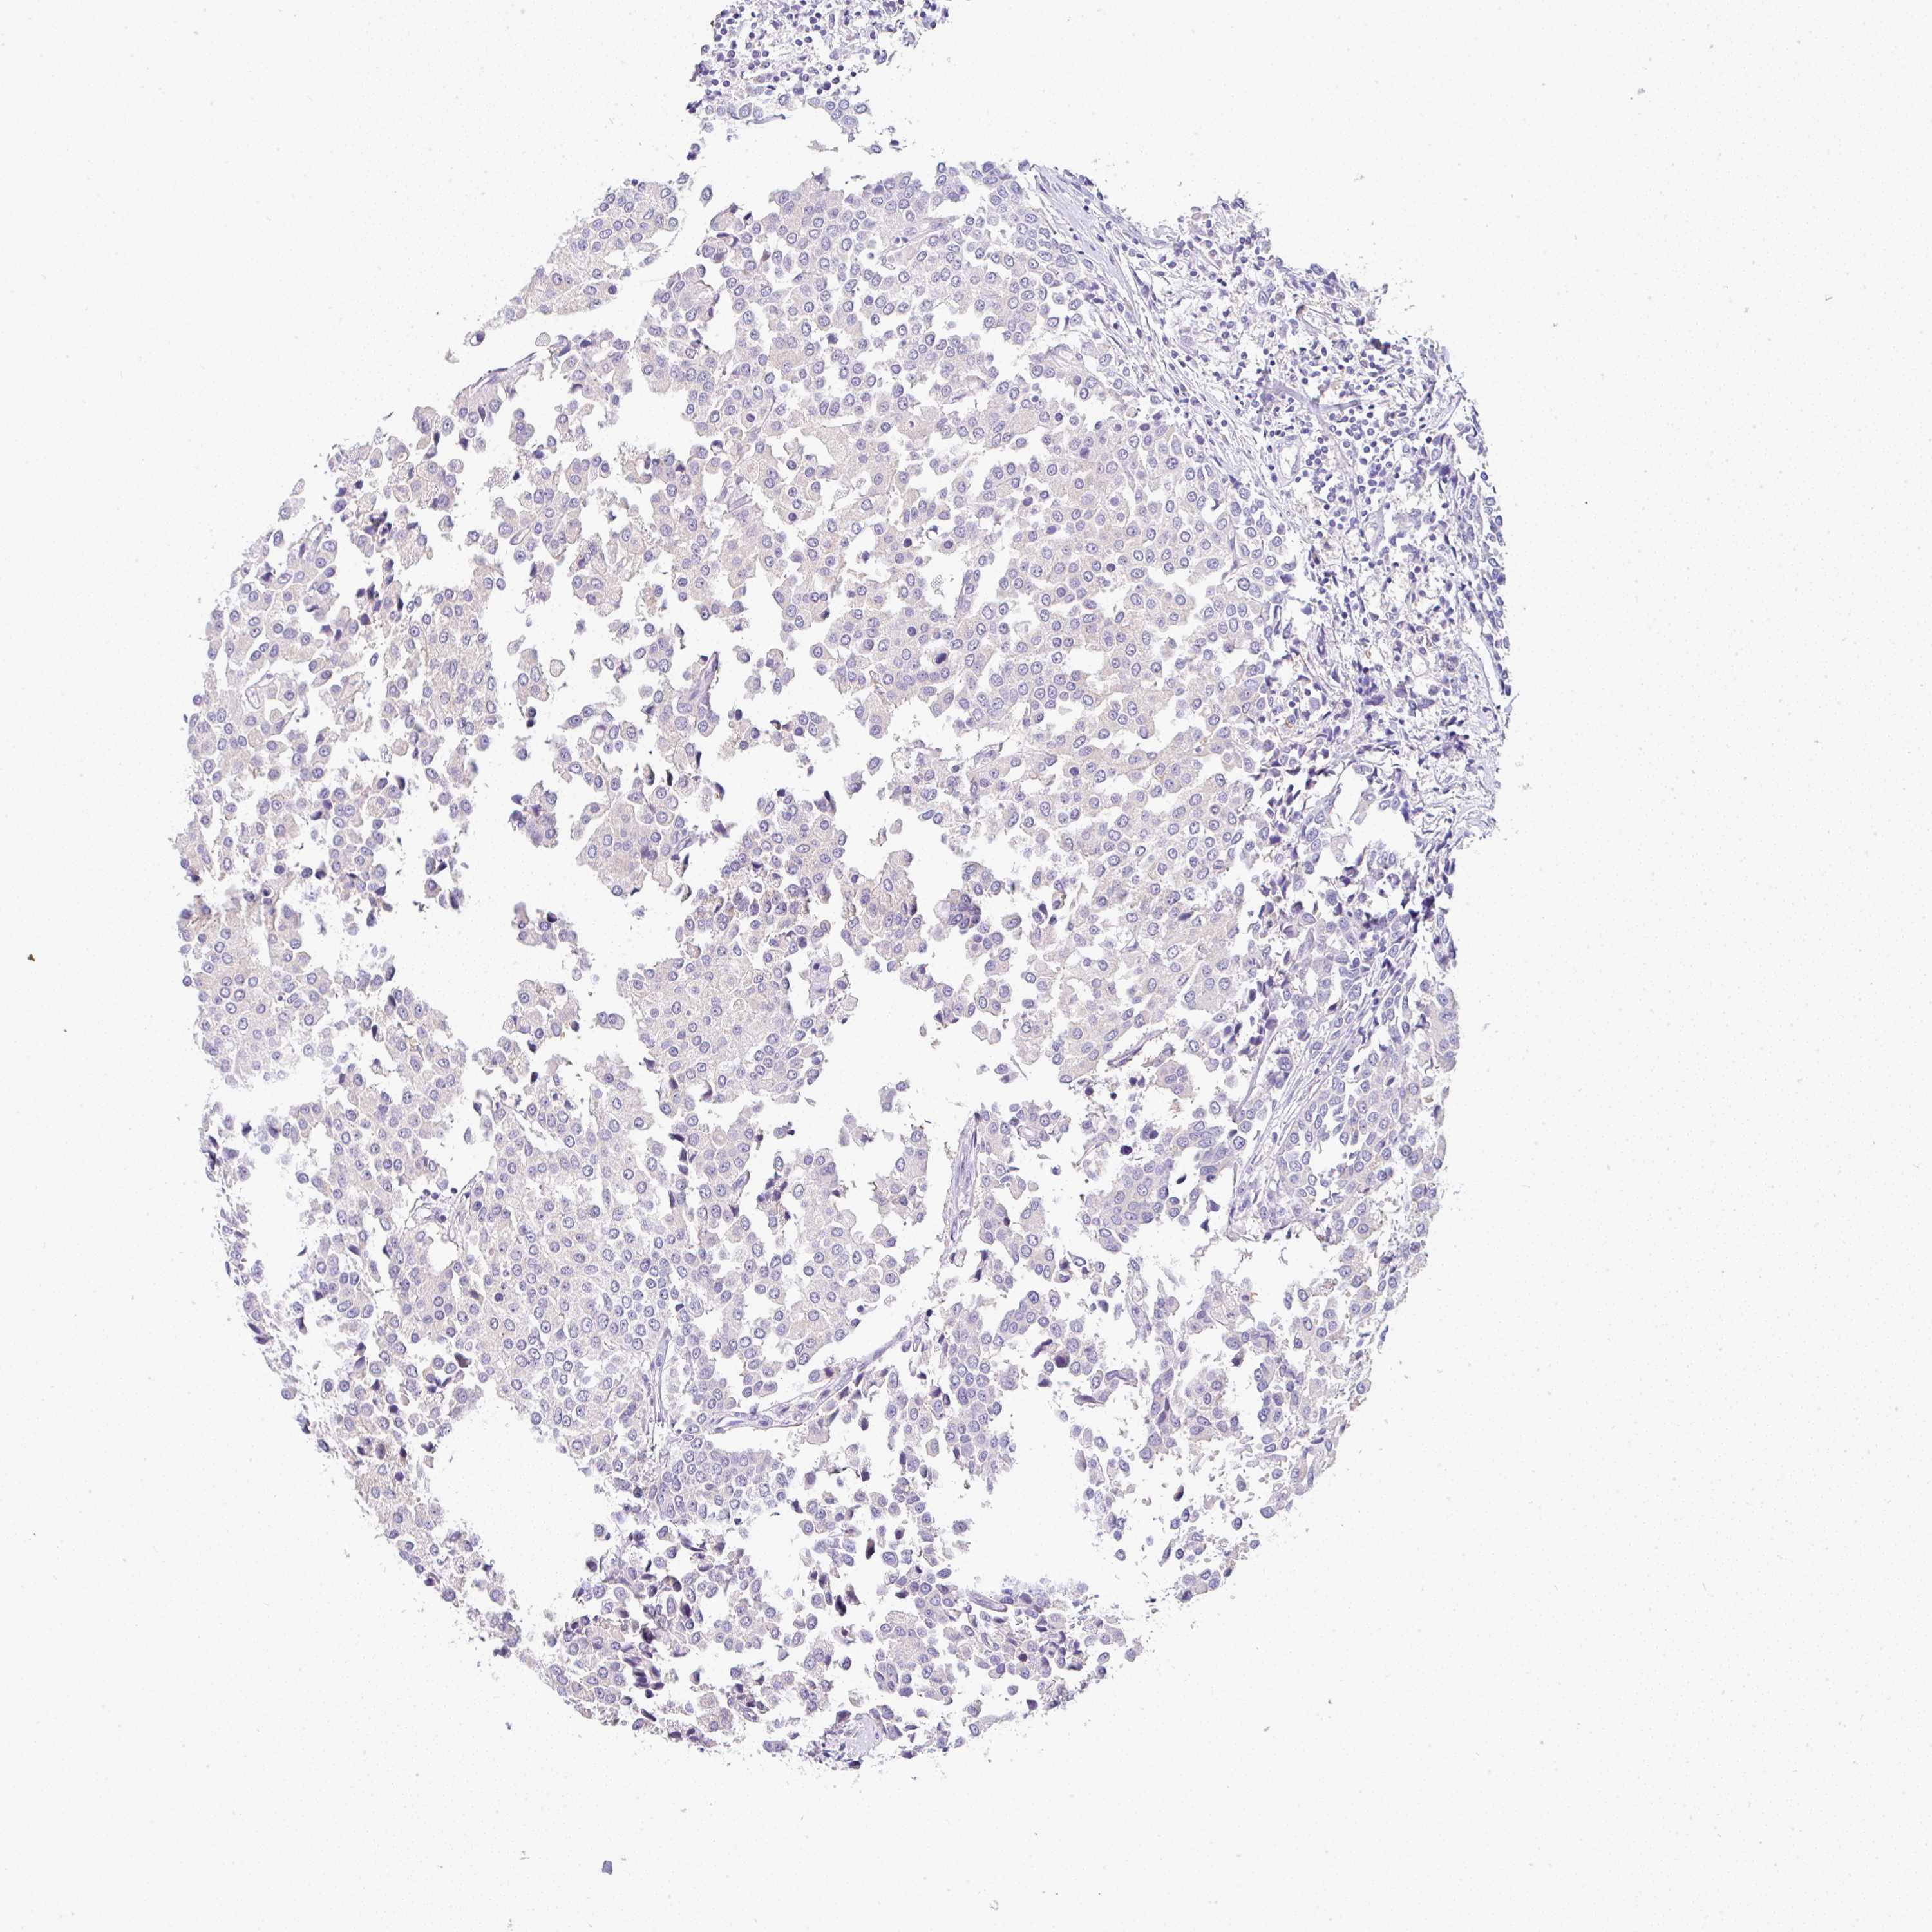

BRCA TCGA BRCA VALIDATION PROTEIN EXPRESSION

ANTIBODIES

AND

VALIDATION